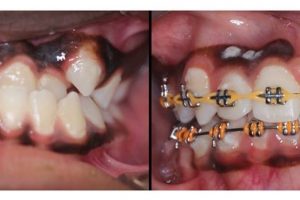

Another great example of why early detection is important!!! Early detection prevented damage to roots, prevented the extraction of teeth, and prevented the need for surgical intervention!! The lower …